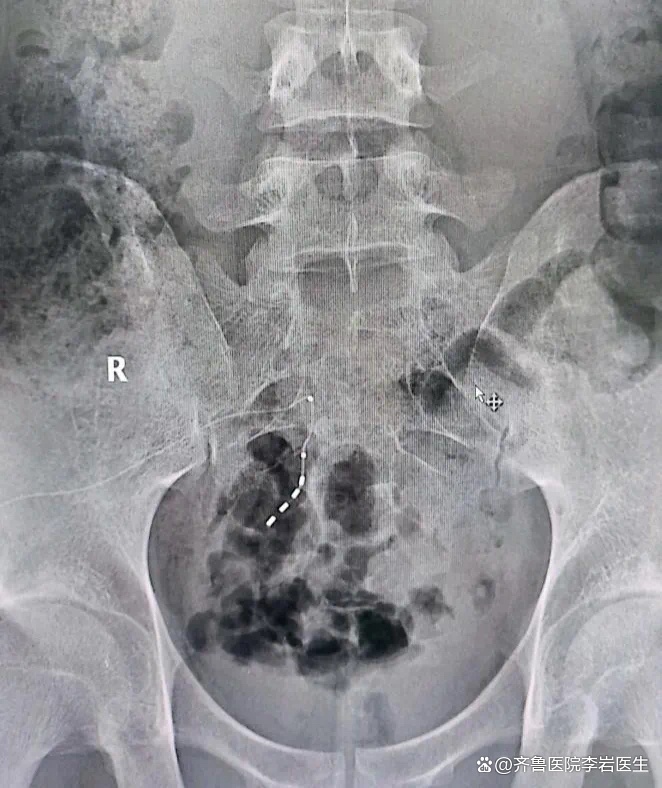

∩^∩ 下肢无力、小便困难? 极为罕见!神经内科医生识破“脑梗”假象!突发肢体无力,不一定是常见的“脑梗”! 55岁的陈大叔,平常除了高血压,身体各方面都棒棒的。半个多月前突然肢体无力伴有排尿障碍,家人以为是“脑梗”了,抱着离家近、检查快的想法,到当地医院经相关检查及治疗后症状未见好转,并开始出现双下肢无力,且大小便失禁的症状。 从“脑...